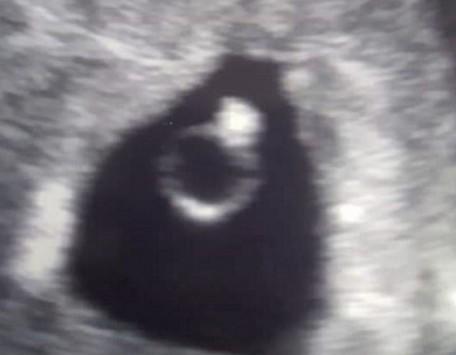

عمان 1 : في واقعة غريبة من نوعها كشفت سيدة أنها حامل في خاتم ماسي، حيث شاهدته كذلك أثناء الفحص الطبي بعد مرور خمسة أسابيع فقط من الحمل.

وكيري ويب البالغة من العمر 24 عامًا من نورويتش الإنجليزية خضعت لفحص طبي بعد مرور خمسة أسابيع من حملها وظهر الطفل في أشعة “السونار” على شكل خاتم ماسي، واعتقدت الأم أن جنينها أراد بهذه العلامة أن يخبرها بأنه سيكون بخير، حسب موقع (ديلي ميل).